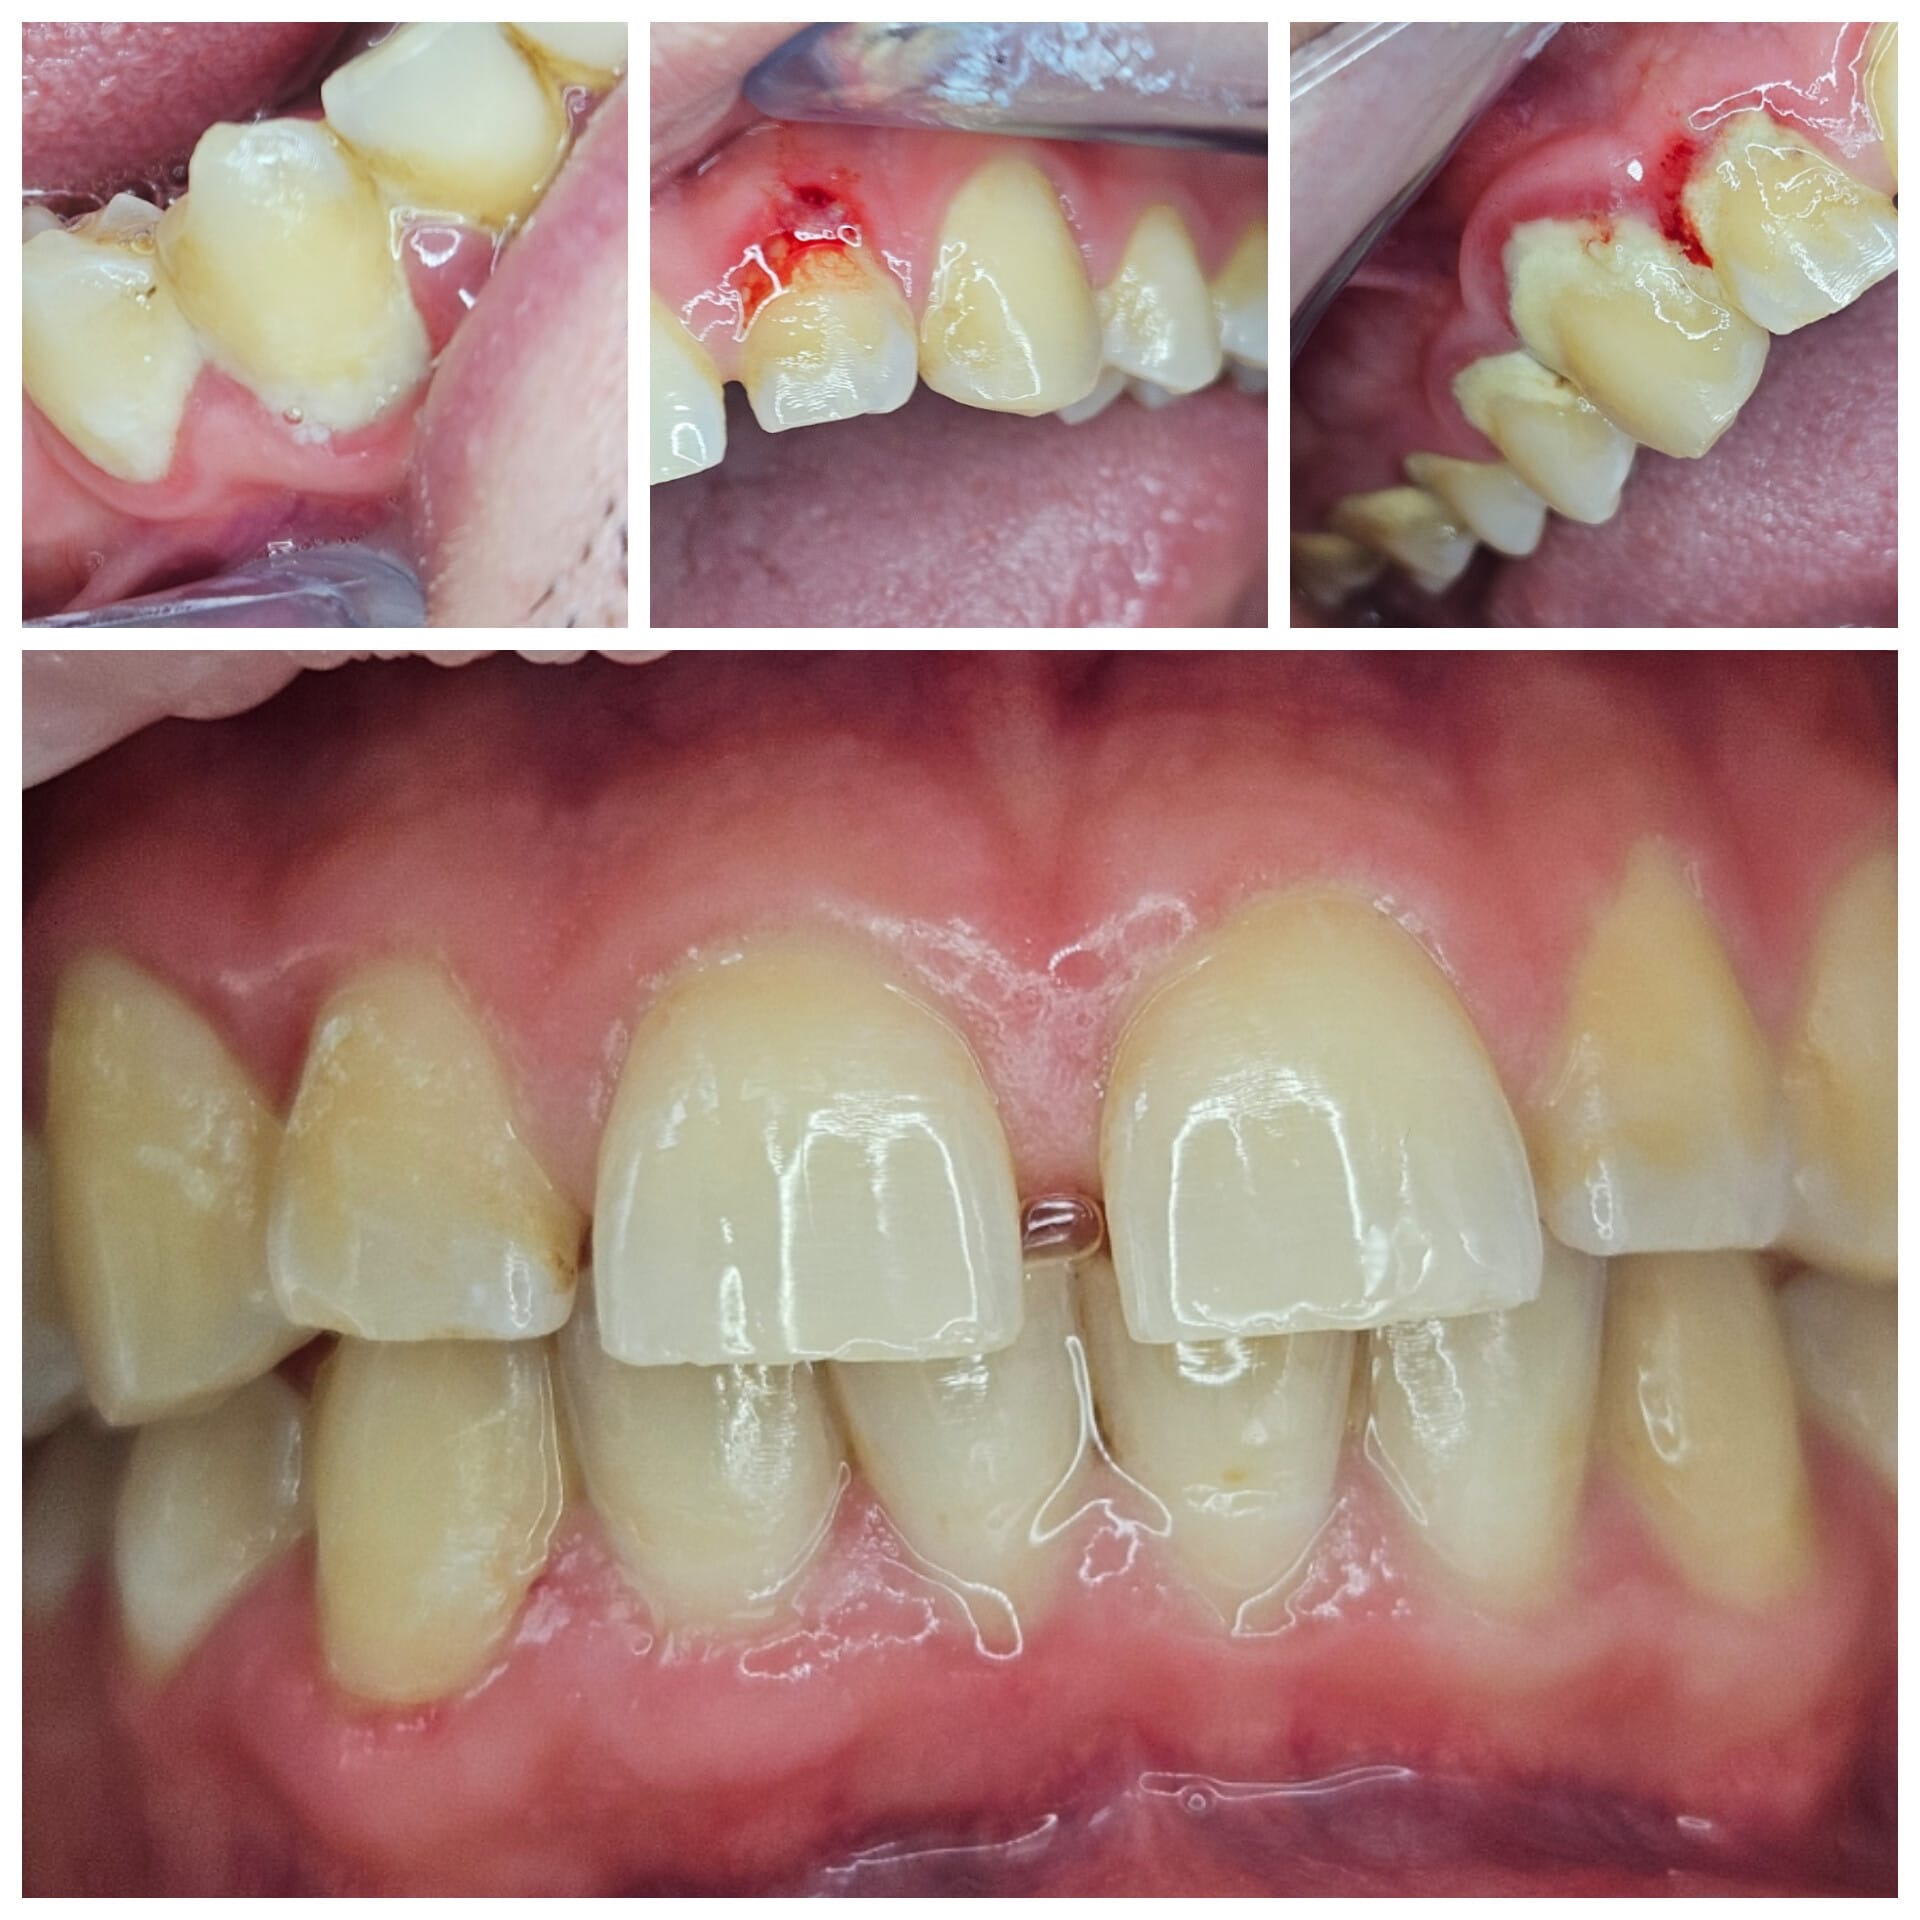

Acestea sunt simptomele parodontozei, o afecțiune care, dacă este ignorată, poate duce la tratamente mult mai complexe și costisitoare!

Parodontoza debutează adesea cu gingii roșii, umflate și care sângerează ușor la periaj sau folosirea aței dentare. Pe măsură ce boala progresează, pot apărea retracții gingivale, mobilitate dentară și respirație urât mirositoare. Dacă observi aceste semne, este esențial să consulți un specialist pentru un diagnostic și tratament adecvat.